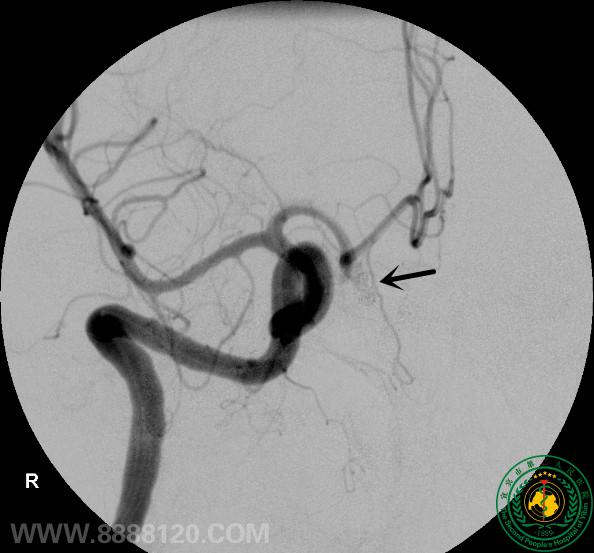

我科成功完成1例复杂前交通动脉瘤的介入治疗

我科成功完成1例复杂前交通动脉瘤的介入治疗9455